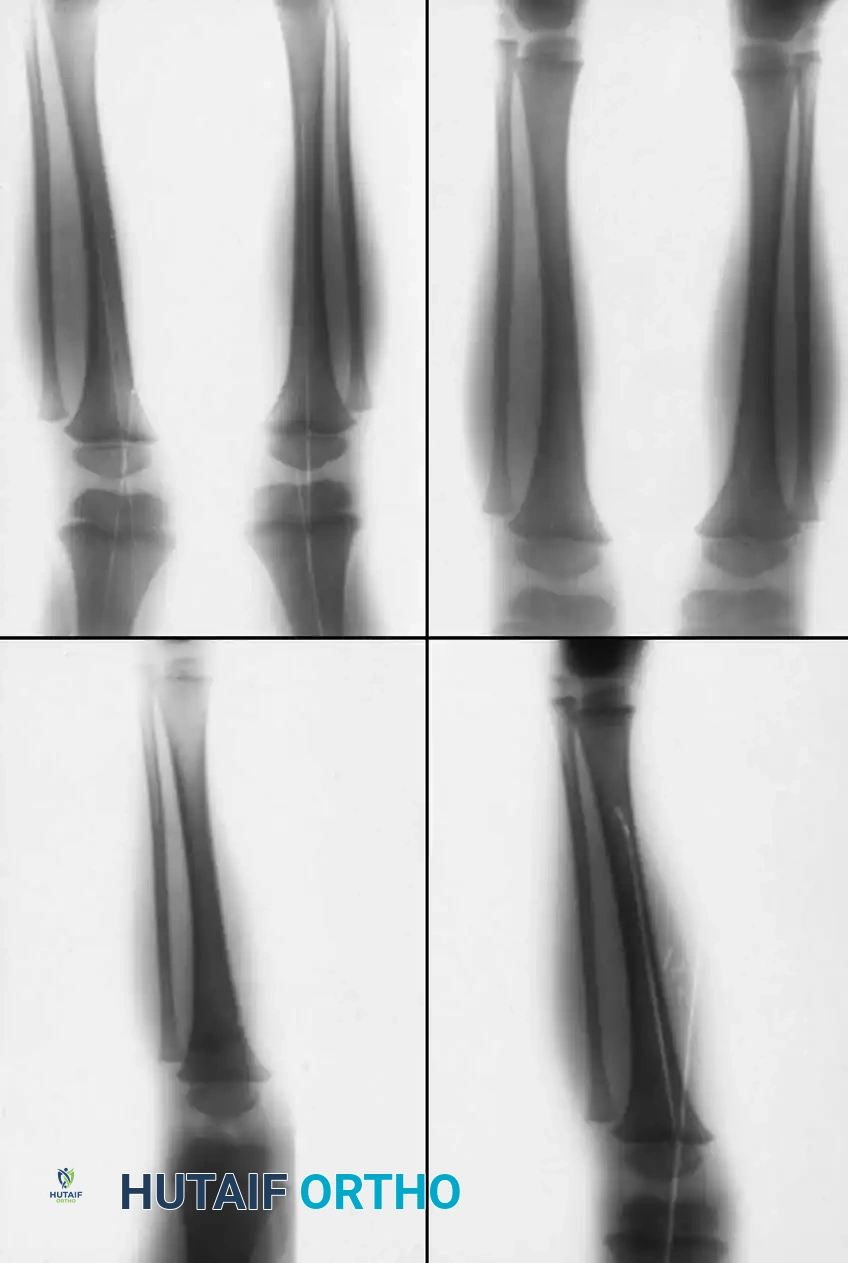

Acute dislocations of the knee and the proximal tibiofibular joint are exceedingly rare in the pediatric population. Unlike adults, where ligamentous failure leads to true tibiofemoral dislocation, the pediatric knee typically fails through the biomechanically weaker physes (growth plates) of the distal femur or proximal tibia. Consequently, what may clinically appear as a knee dislocation in a child is frequently a displaced physeal fracture.

Pediatric fractures of the tibia and fibula generally possess an excellent capacity for remodeling and can predominantly be treated via closed reduction and cast immobilization. Operative intervention is strictly indicated when fractures are irreducible, open, associated with compartment syndrome, or involve the proximal or distal tibial physes with unacceptable displacement.

1. Ligamentous Anatomy: Fewer ligaments attach directly to the proximal tibial physis compared to the distal femoral physis. The medial collateral ligament (MCL) inserts distally onto the tibial metaphysis, bypassing the physis. Consequently, the distal femoral physis separates far more frequently than the proximal tibial physis (a ratio of approximately 8:1 in major trauma centers).

Wozasek et al. reported that 13% of patients with proximal tibial physeal injuries exhibited peripheral ischemia. Immediate vascular assessment (Ankle-Brachial Index, Doppler ultrasound, or CT angiography) is mandatory for any displaced proximal tibial fracture.

Canale and Shelton's extensive review of proximal tibial epiphyseal fractures highlighted that these injuries typically occur in older children (average age 14.2 years) approaching skeletal maturity.

- Type I and II Fractures: Most can be managed with closed reduction and a bent-knee cast. However, posterior displacement requires meticulous reduction to relieve arterial tension. Unacceptable angulation must be corrected; malunion in older children will not remodel sufficiently.

Advanced imaging (CT with sagittal and coronal reconstructions, or MRI) is critical to determine the exact fracture geometry and the degree of articular step-off. Plain radiographs often underestimate the severity of the displacement, providing a false sense of security.